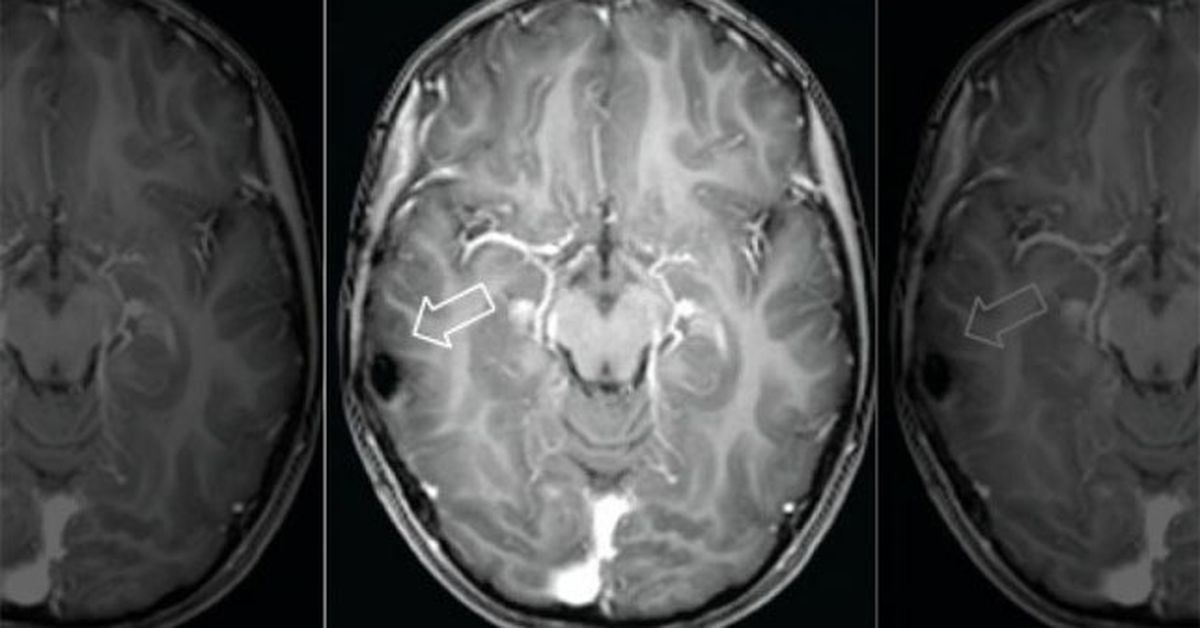

Если вы заметили у своего кота подобные симптомы, немедленно обратитесь к ветеринару. Специалист сможет провести комплексное обследование, включающее нейрологическое исследование, рентген, магнитно-резонансную томографию и биопсию, для определения наличия и характера опухоли головного мозга вашего кошки.

Лечение опухоли головного мозга у кота обычно требует комплексного подхода и может включать хирургию, химиотерапию и радиотерапию. Однако, проведение точного диагноза с помощью методов, таких как компьютерная томография или магнитно-резонансная томография, является важным шагом в определении наилучшего метода лечения для вашего кота.